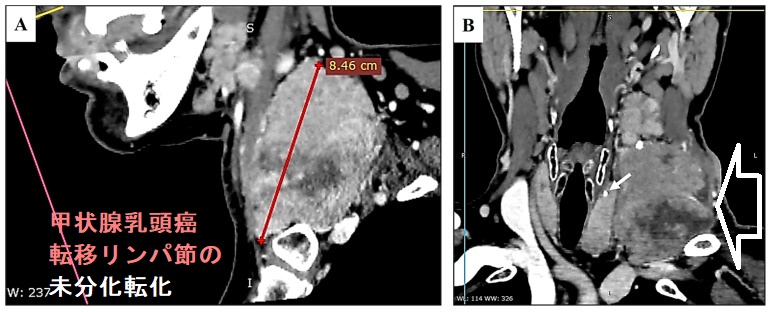

甲状腺乳頭癌の未分化転化は、0.8–2% の頻度で起こりえます。甲状腺乳頭癌の肺転移巣・遠隔転移巣や転移リンパ節が未分化転化する報告は多くあります[Ann Diagn Pathol. 2010 Feb;14(1):41-3.][J Surg Oncol. 1999 Jan;70(1):45-8. ]。